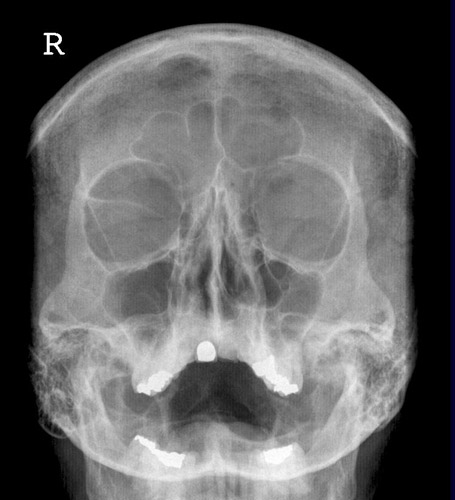

Orbita Übersicht

Fehler

Schräge Projektion, d.h. ungleicher Seitenabstand der Schädelkapsel zum Orbitarand. Die Orbitae stellen sich ungleichmäßig dar. Die Außenränder der Orbitae lassen sich nicht richtig vergleichen.

Abhilfe

Der Kopf war zwar richtig für eine Orbita gelagert, doch etwas nach links verkippt. Bei klinischer Relevanz müsste noch mal eine richtig orthograde Einstellung erfolgen.